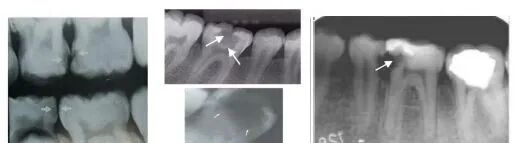

牙髓疾病 dental pulp disease:

牙内吸收

曲面断层片怎么看正畸【曲面断层片(全景片)】如何解读和查看:牙周?牙体?牙髓?关节?_https://www.jmylbn.com_新闻资讯_第4张

患牙髓腔扩大,呈圆形/卵圆形/不规则形密度减低透射影。发生于根管者有长短不一、粗细不均、沿根管的扩大影。髓室壁或根管壁变薄。可伴有根尖吸收/感染/折断。

牙髓钙化

曲面断层片怎么看正畸【曲面断层片(全景片)】如何解读和查看:牙周?牙体?牙髓?关节?_https://www.jmylbn.com_新闻资讯_第5张

阻射影;后牙为圆形、卵圆形,可游离于髓室内,也可附着于髓室壁;前牙为条状或针状,充满于髓室或根管内,周围有线状低密度影像环绕。

曲面断层片怎么看正畸【曲面断层片(全景片)】如何解读和查看:牙周?牙体?牙髓?关节?_https://www.jmylbn.com_新闻资讯_第6张

正常髓室及根管影像完全消失,不能辨别出髓腔界线,有的尚可见,但很细。